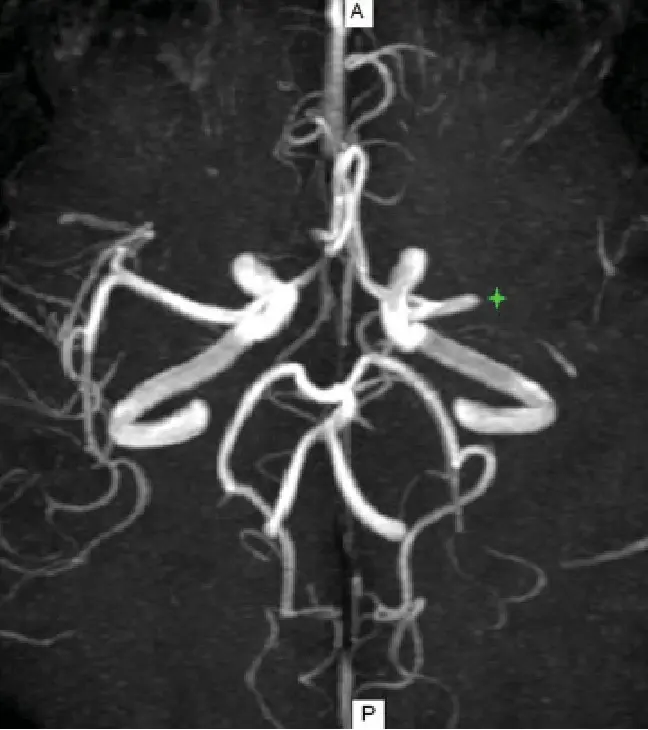

Angioresonancia Magnética en Caracas: Información, Precios y Beneficios Es un procedimiento avanzado de diagnóstico por imágenes que permite visualizar los